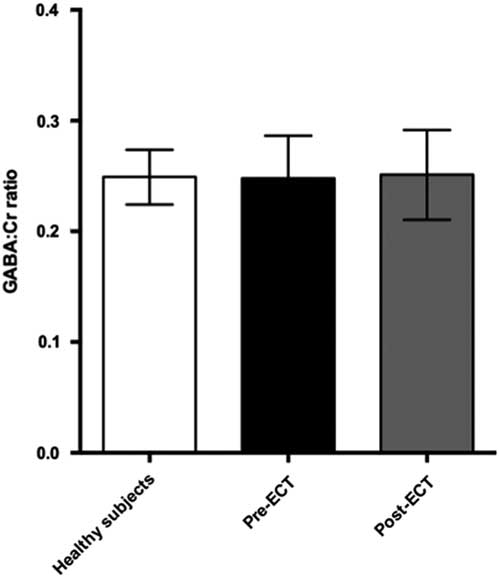

GABA measurements in PFC

Fig. 4 Plot of GABA:Cr ratios in prefrontal cortex showing mean ± SD. ECT, electroconvulsive therapy; GABA, γ-aminobutyric acid.

Comparing pre- and post-ECT GABA/Cr levels, we found no significant changes (t=0.10, p=0.92) as the mean GABA/Cr ratio was 0.249 (±0.04) pre-ECT, and 0.251 (±0.04) post-ECT. There was no correlation between changes in HAM-D17 rating scores and the fractional GABA/Cr changes [(GABApost−GABApre)/GABApre] (r(8)=0.43, p=0.21). Moreover, no significant correlation was found between pre- or post-ECT GABA/Cr levels and HAM-D17 ratings (p=0.77 and p=0.236, respectively).